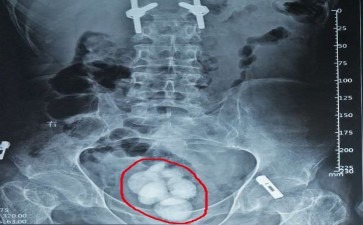

你是否曾在深夜被一阵突如其来的尿意惊醒,却发现自己排尿时像被针扎一样疼?又或者,你发现自己尿液中混着血丝,吓得赶紧去医院?这些“不速之客”——长春碎石医院膀胱结石,可能就是背后的“捣蛋鬼”。长春碎石医院膀胱结石,顾名思义,就是在膀胱里形成的... [详情] 电话:0431-81168858

你是否想过,膀胱这个“尿液仓库”里,可能藏着一群调皮的“小石子”——长春结石医院膀胱结石?它们不声不响,却能在关键时刻让你疼得直不起腰,排尿变得像“闯关”一样艰难。长春结石医院膀胱结石的形成,和我们的生活习惯、身体状况息息相关。长期憋尿、喝... [详情] 电话:0431-81168858

长春碎石医院膀胱结石为啥这么爱“搞破坏”呢?原来,它形成的原因可不少。要是你平时喝水太少,尿液长时间浓缩,里面的矿物质就会像调皮的孩子一样,慢慢聚集在一起,形成结石。还有,要是你爱吃高草酸、高嘌呤的食物,像菠菜、动物内脏,也会让尿液里的相关... [详情] 电话:0431-81168858